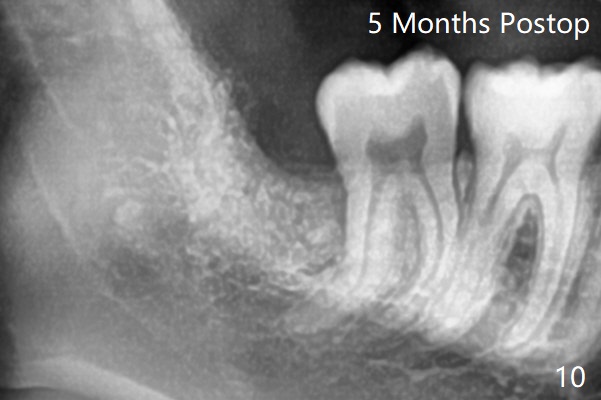

A 19-year-old man returns for #1,16,17 and 32 extraction (Fig.1,2). Because of horizontal impaction of #32 and no bone #31 distal post extraction (Fig.3 *), 3D bond (.5 cc) will be placed in the mesial socket of #32 (Fig.4 red), while Osteogen plug (1/2 (O)) in the distal one. Since there is no bony defect between #17 and 18 after extraction (Fig.5 *), a piece of Osteogen plug (cut half apical) will be inserted in #17 socket, whereas 2 small pieces of Osteogen plug placed in the apical portions (triangle and spindle shaped). Take posterior panoramic X-ray postop (bitewing type, CT format, not XV). There appears bone formation in the socket 5 months postop (Fig.10,11).

Since #32 sockets seem large, extending mesiobuccal (Fig.6), Bond Apatite (1 cc) is placed instead (Fig.7 B), covered by 1/3 of Osteogen plug (O) and sutured with 4-0 PGA. Extraction of #17 is also difficult. As 2 sockets are indistinct, a piece of Osteogen plug with split is placed (Fig.8) upside down (Fig.9 vs. Fig.5). There appears bone formation in the socket 5 months postop (Fig.10,11).